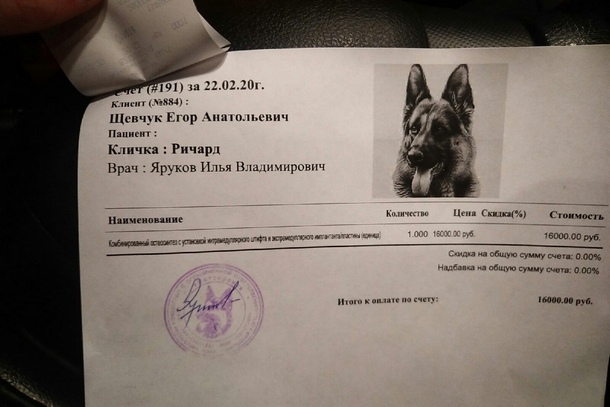

По ее словам, чтобы провести операции, ветеринары задержались в клинике до позднего вечера. Собаке поставили две металлические пластины. Услуги клиники обошлись в 16 тысяч рублей. Благодаря объявленному добровольцами в соцсети сбору средств, часть расходов удалось компенсировать.

Спасители назвали щенка Ричардом. Минувшей ночью они вернулись в Сосногорск. Сбор средств на лечение собаки на момент подготовки материала был открыт.